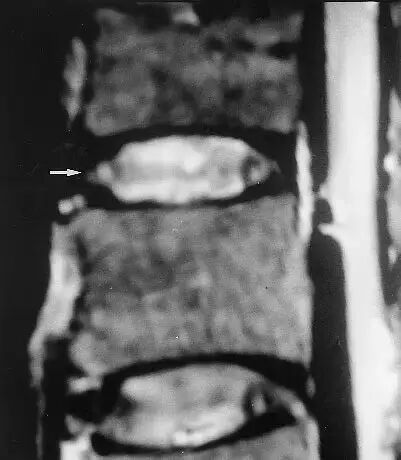

当前的MRI技术主要按质子(氢)的分布情况成像,首先反应组织的含水量。此技术的优点包括能显示椎管内肿瘤、检查全脊柱并能根据含水量的减少来确定椎间盘的退行性改变。

Szypryt等人发现在诊断脊柱疾病方面,MRI稍优于脊髓造影,MRI的准确率是88%,脊髓造影是75%; MRI在诊断椎间盘退变、肿瘤和炎症方面有明显的优势。大部分MRI扫描图像能够显示一个完整的脊柱节段(如颈段、胸段或腰段)而不是三段都显示,也能清楚地显示椎间孔部位和椎旁的软组织。

MRI非常准确,能在病人无症状时发现多种病变。Gibson等人发现在所有有症状的青少年中均有椎间盘退变,20名无症状的青少年中4名有椎间盘退变。Boden发现无症状病人中颈椎异常者在40岁以下占14%,40岁以上占28%;颈椎椎间盘退变在40岁以下为25%,60岁及60岁以上占60%。

他们研究了67例无症状病人的腰椎MRI图像,发现在60岁以下人群中腰椎间盘髓核突出者为20%,在超过60岁的人中有36%的人有髓核突出。60岁及60岁以上的被检查患者中有57%为无症状的异常;腰椎间盘退变在20~39岁年龄组为35%,50岁以上为100%。因此,必须将影像学的发现与临床的发现仔细联系在一起。